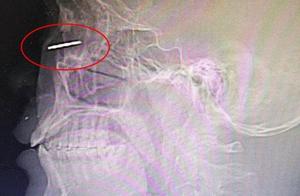

The diameter discovers inside skull 7 centimeters eyewinker, bring about disposition to change great